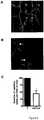

• Figure 3. Overexpression of hsa_miR_27a disruptsin vitro tube formation. HUVEC were transfected with either a pre-miR negative control (A) or with a precursor for hsa_miR_27a which allowed its overexpression (B). 24h post transfection cells were plated onto Matrigel™ and observed over a 24h time period. Areas where tubes were not able to join and make a stable network are indicated with white arrows. Very thin tubes are indicated by black arrows. (C) Number of capillary tubes formed per field of view quantified. Results shown are the mean of four independent HUVEC lines ± SEM. *, p<0.05 control vs miR_27a.

• As shown inFigure 3, overexpression of hsa_miR_27a disruptsin vitro tube formation. HUVEC were transfected with either a pre-miR negative control (Figure 3A) or with a precursor for hsa_miR_27a which allowed its overexpression (Figure 3B). Both control and miR_27a transfected cells were seen to realign within the first 6 hours as normal. However, the cells overexpressing miR_27a failed to extend and mature (Figure 3B). By 12 hours, miR_27a overexpressing cells showed thin projections which often failed to join, tubes that had formed within this period were breaking apart and there was a significant decrease in the number of fully formed capillary tubes (Figure 3C). These results indicate that the downregulation of miR_27a is necessary for stable capillary tube formation and maturation to occur.